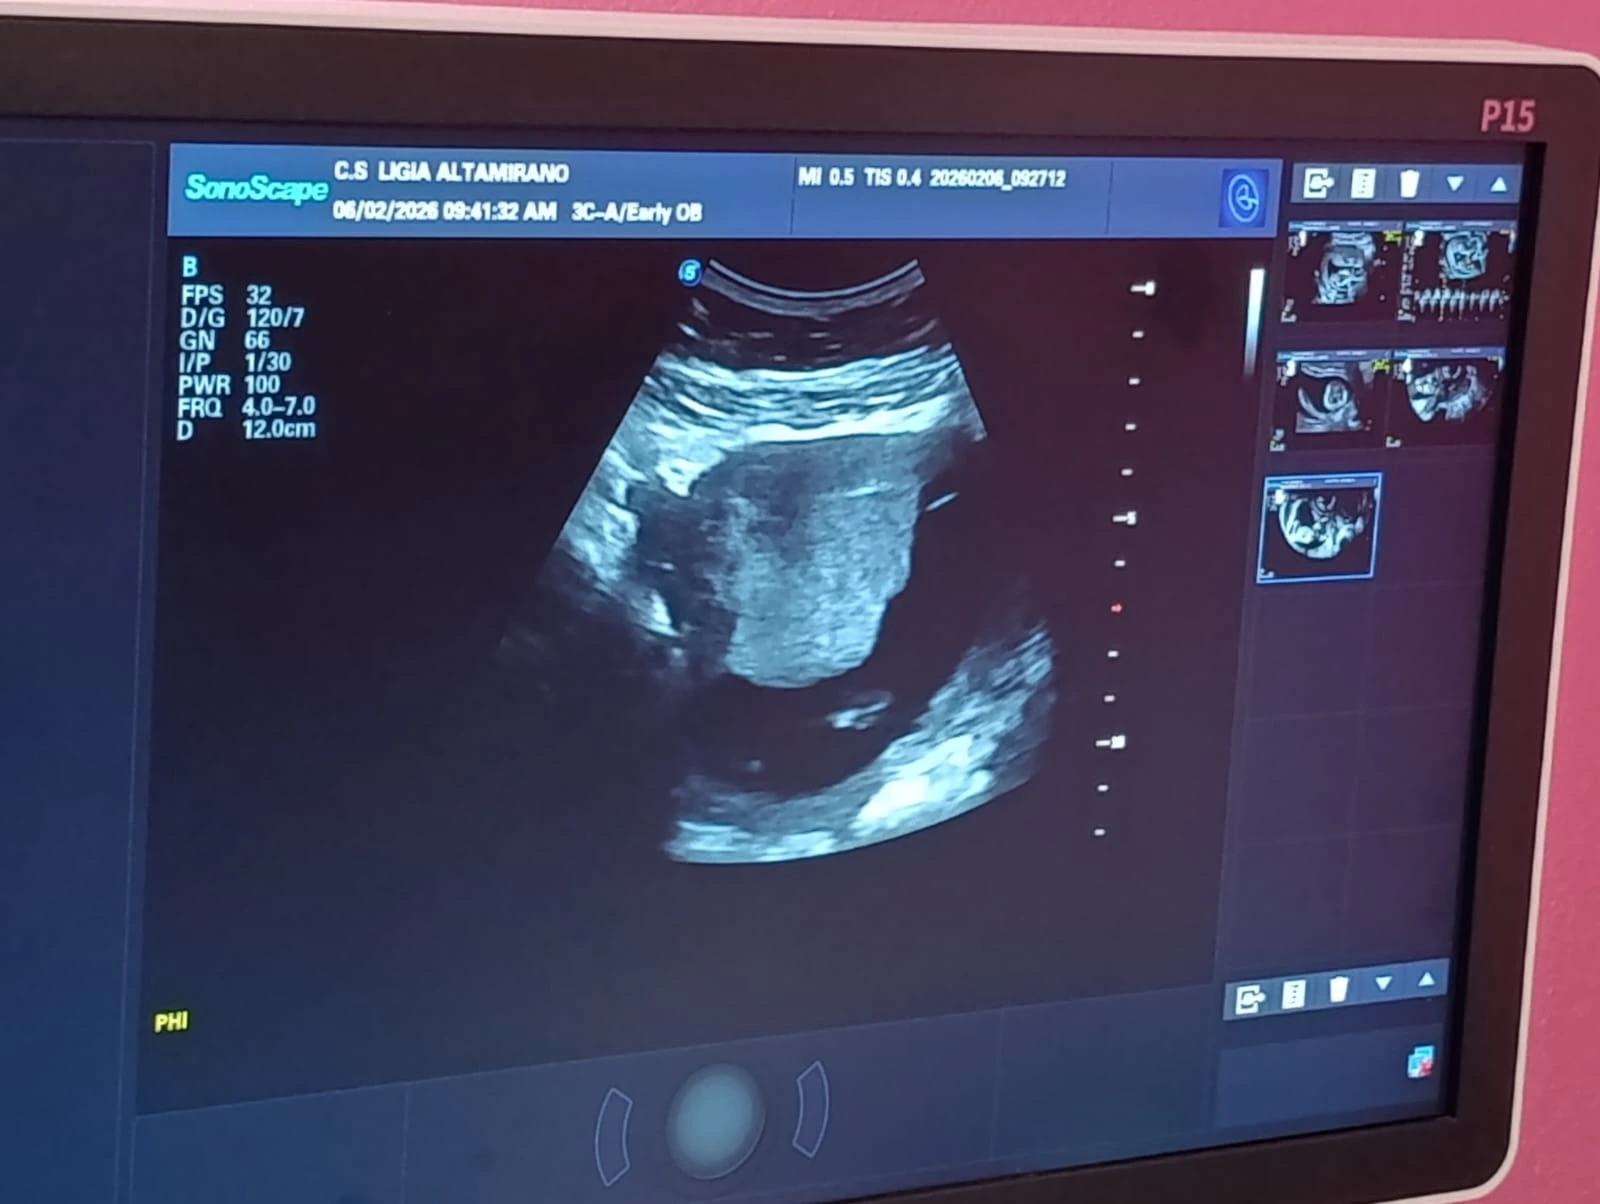

“Este estudio aplica la realización de un tamizaje del primer trimestre que consiste en la realización de ultrasonido obstétrico, en donde se valora la edad gestacional del bebé, y también se utiliza el tamizaje de arterias uterinas para valorar el riesgo a desarrollar preclampsia en la embarazada y, por último, lo que es la medición de la longitud cervical, que ayuda a valorar las pacientes que tienen un alto riesgo de desarrollar un parto pretérmino”, aseguró García.

“Venimos a realizar el chequeo médico y ultrasonido para ver que el bebé no venga con ningún defecto y esto es algo bueno que nos brinda nuestro Comandante para que estemos bien”, señaló.